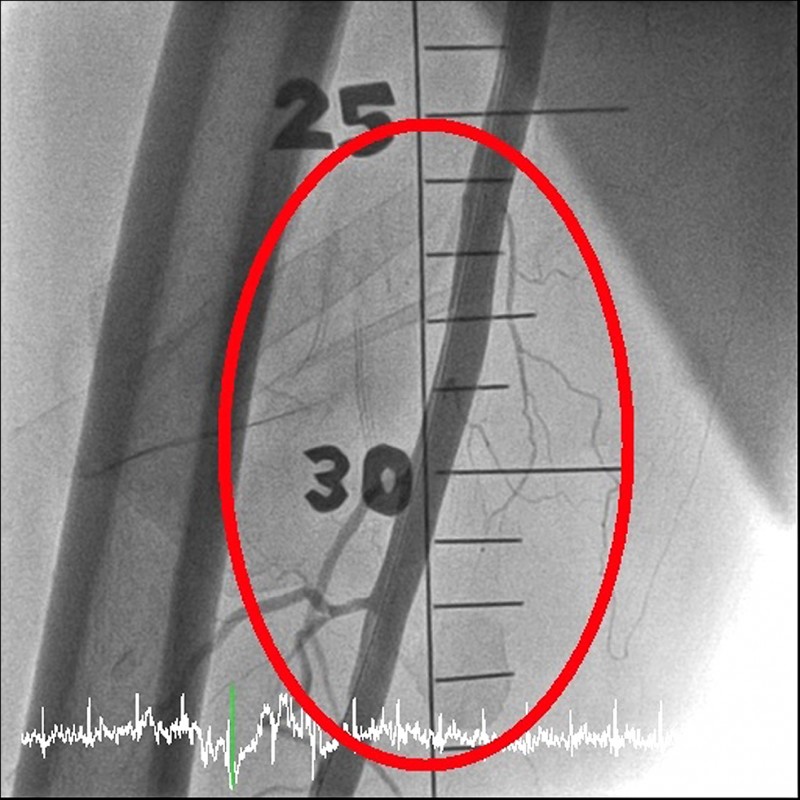

苗栗縣71歲陳姓老翁,從年輕時,就有抽菸習慣,是老菸槍,1週前突然覺得右腳冰冷、麻木,且小腿越來越痛,就醫檢查發現,他的右腳動脈被血栓塞住,導致大腿以下完全沒有血流。所幸,經醫師以「微創噴射機械除栓」手術,搭配導管溶栓治療,成功移除血栓、打通血管,保住他的右腳,免於被截肢的命運。

楊智鈞表示,過去傳統治療方式為使用藥物及開刀清除血塊,但出血風險很高,現行新技術「噴射機械除栓」設備,可以用微創的方式伸管子到血管裡把血塊清乾淨,再搭配藥物輔助,較傳統治療安全、成功率也較高。